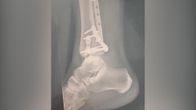

Эллисон Медейрос ехал на своем велосипеде домой с работы в плетеных районе парка около 5:30 вечера 20 июня, по словам его адвокатов. Он ехал с потоком движения по велосипедной дорожке, когда наездник скутера — движущуюся в противоположном направлении на той стороне дороге, врезался в него. Скутер гонщик скрылся. Но Медейруш был доставлен в больницу с множественными разрывами в его челюсти, носа, орбиты и неба и рваные раны, требующие более 20 швов. Ему пришлось несколько операций.